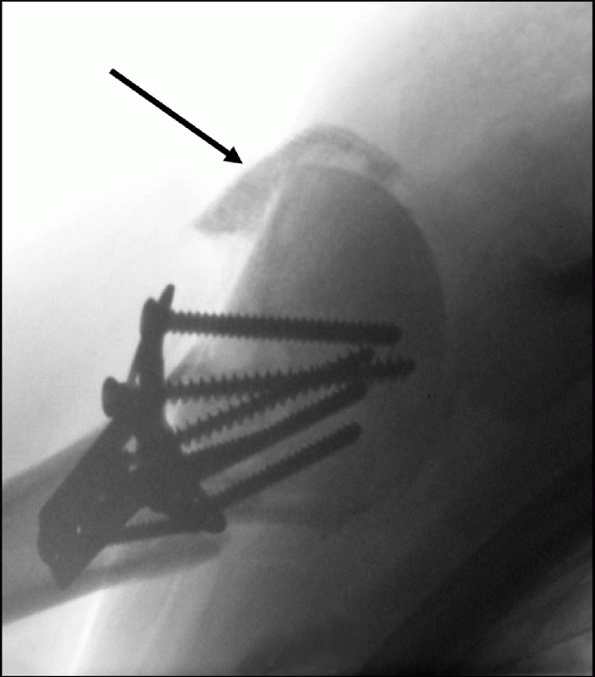

![]() |

|

FIGURE 35-18

In Type I anterior fracture-dislocations, the humeral head is engaged on the anterior glenoid rim, as shown on the anteroposterior radiograph (A), the schematic diagram (B), and anteroposterior and superior three-dimensional computed tomography reconstructions (C,D). Internal fixation of these fractures is associated with a low risk of osteonecrosis (E,F). (continues) |

FIGURE 35-18 (continued)

In Type II anterior fracture-dislocations, the humeral head is not engaged on the anterior glenoid rim, as shown on the anteroposterior radiograph (G), the schematic diagram (H), and anteroposterior and superior three-dimensional computed tomography reconstructions (I,J). The humeral head dislocates through a rent in the inferior capsule (K). (continues) |

It is usually devoid of soft tissue attachments and at higher risk of osteonecrosis. Iatrogenic displacement of the initially impacted shaft from the head may occur during attempted relocation of the shoulder, as seen on these premanipulation and postmanipulation radiographs that were taken in the emergency department (L,M). |